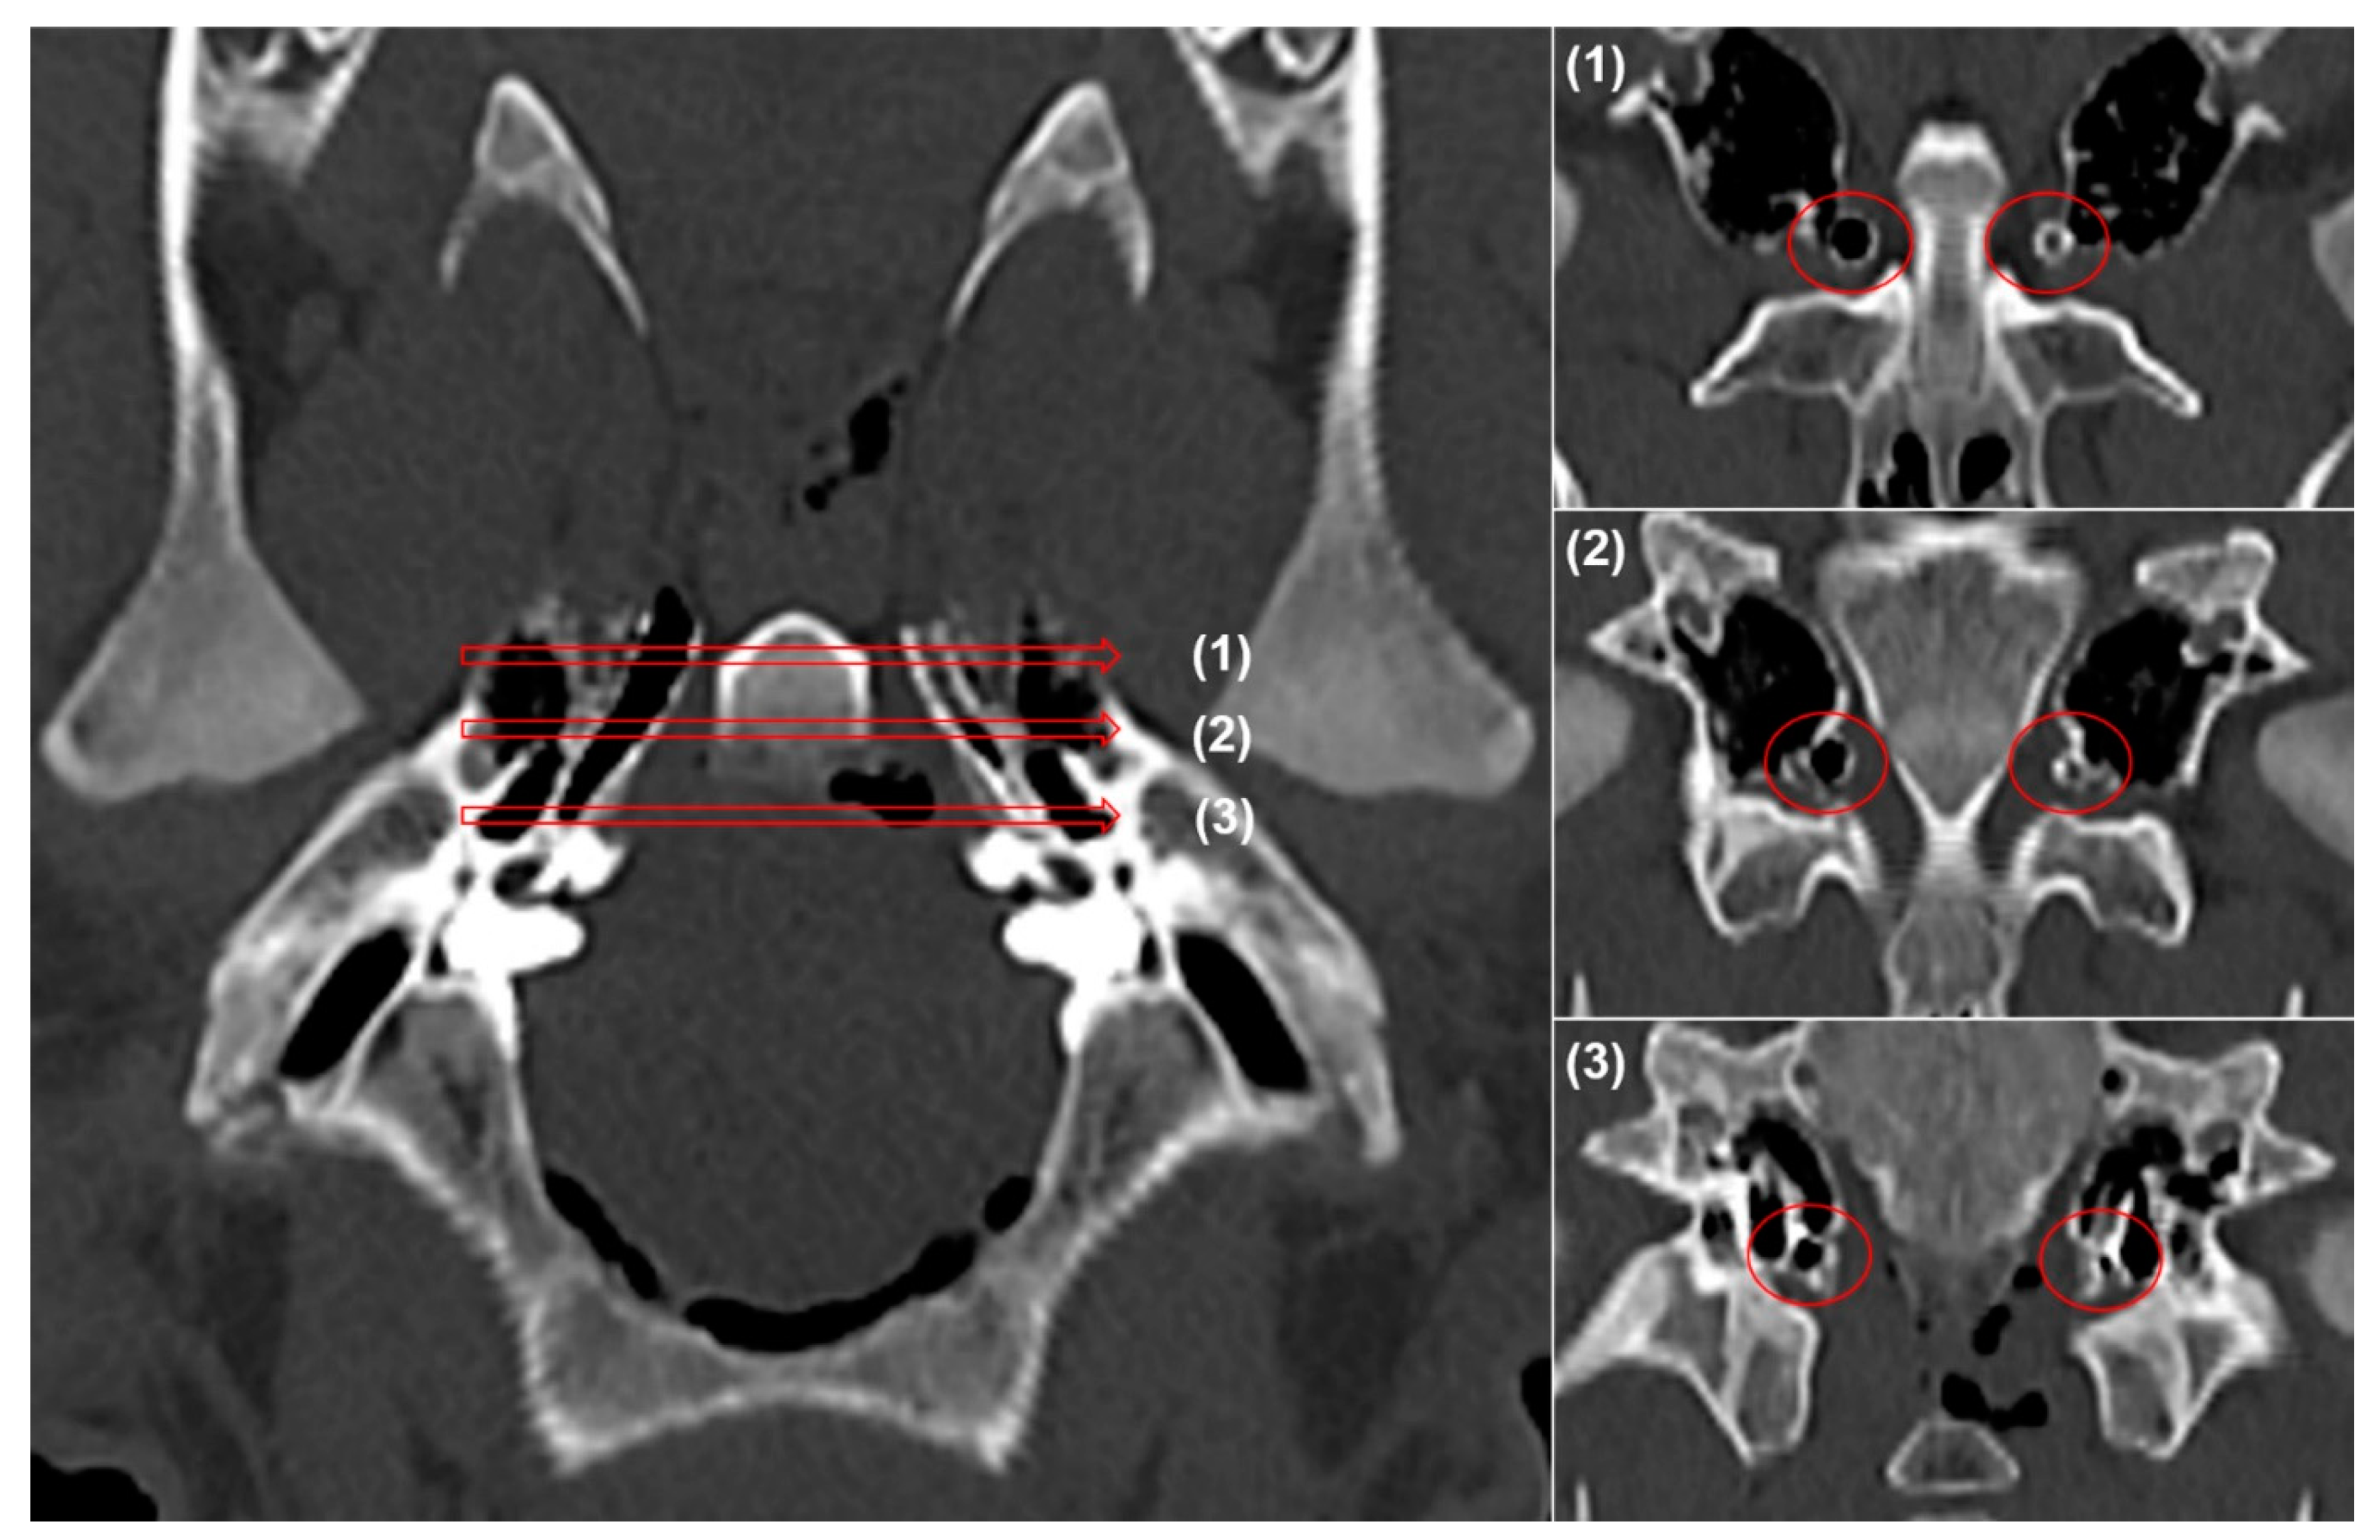

| Stent Diameter/Site | Location | Luminal Diameter (mm) | Decrease Rate (%) |

|---|---|---|---|

| 3.5 mm/Right ET | Proximal | 3.48 ± 0.06 | 0.9 ± 0.8 |

| Middle | 2.54 ± 0.17 | 27.4 ± 7.6 | |

| Distal | 2.15 ± 0.14 | 38.6 ± 4.1 | |

| 2.5 mm/Left ET | Proximal | 2.49 ± 0.04 | 0.4 ± 0.6 |

| Middle | 1.73 ± 0.21 | 30.8 ± 8.3 | |

| Distal | 1.42 ± 0.18 | 43.2 ± 7.1 |